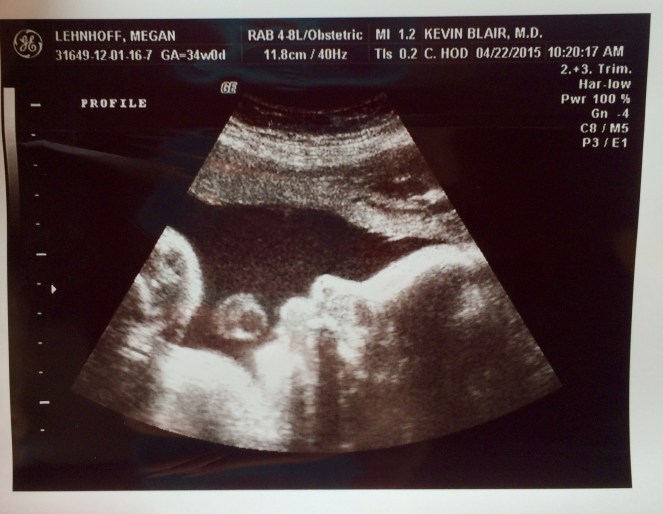

Here’s a profile of baby’s face (at right of screen you will see forehead, nose, and lips as you move left, and the random circle floating above his mouth is the cord).